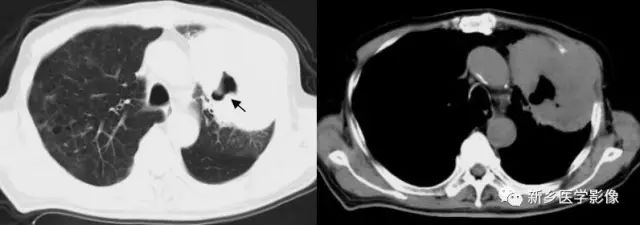

肺脓肿空洞CT图

a. 肺窗;b.纵隔窗,显示右上肺厚壁空洞(↑)周围见大片状模糊影